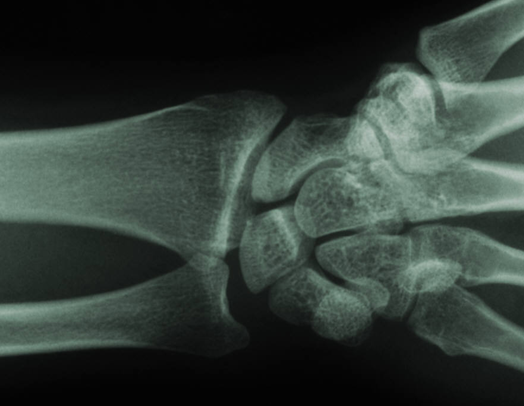

A. Joint pain frequently occurs due to the breakdown of cartilage, a smooth tissue in the joint that acts as a cushion between two bones. As cartilage breaks down, the two bones rub together resulting in inflammation, pain and reduced range of motion. If left untreated, arthritis can lead to long-term joint damage, pain and disability.

A. A popular alternative to oral medications and one that can delay, or in some cases eliminate, the need for surgery is a joint injection procedure. Joint injections combine a corticosteroid and anesthetic agents that can lead to a rapid decrease in pain and inflammation without the side effects of oral medications. In many instances, these minimally invasive and cost-effective treatments can delay and even eliminate the need for surgical intervention.

However, like most procedures, the success of the procedure depends on the expertise of the clinician and the accuracy with which the medications are injected into the affected joint space. Accurate drug delivery may also help reduce the need for repeat injections, which in turn reduces costs and improves patient care. A patient may receive orthopedic injections every few months, as their prescribed method of pain management.